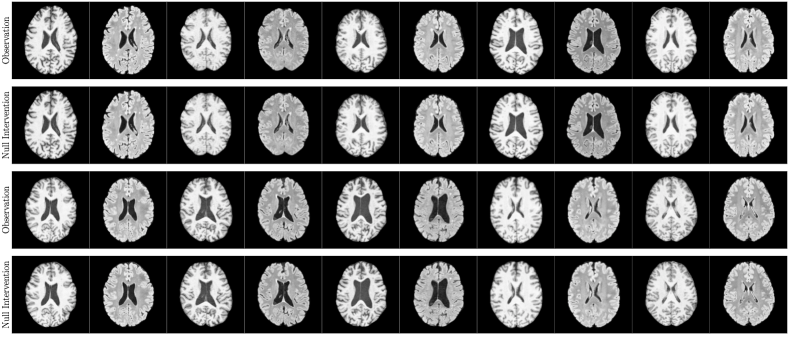

4.2 Brain Imaging Counterfactuals

To demonstrate our model’s ability to produce faithful high-fidelity counterfactuals of real data, we extend our approach to a real-world scenario involving brain MRI scans from the UK Biobank (Sudlow et al., 2015). As before, we start with an assumed causal generative process involving a set of observed variables as shown in Figure 4(a). The causal graph is medically informed and extends the scenario in Pawlowski et al. (2020) by: (i) introducing an additional MRI Sequence (T1/T2) binary variable to enable discrete counterfactuals; (ii) having directly. We used a scaled-up version of our exogenous prior HVAE as ’s mechanism and used (conditional) normalizing flows for the other mechanisms (see Appendix A.1). As shown in Figure 4, our deep SCM is capable of producing qualitatively sharp counterfactuals with localised changes according to the intervened upon parent(s) and the associated causal graph. Importantly, the identity of subjects is well preserved in all cases including null-interventions (i.e. nothing). Table 2 shows the counterfactual effectiveness results from random interventions on each variable. We observed satisfactory initial counterfactual effectiveness and significant improvements of post counterfactual training, demonstrating the merit of the proposed approach. Please refer to Appendix A.2 for notes on abduction uncertainty and D for additional results.

D.3 Extra Results

‘MRI Seq.’ counterfactuals

Post counterfactual training:

‘Sex’ counterfactuals

‘Age’ counterfactuals

‘Brain Volume’ counterfactuals

‘Ventricle Volume’ counterfactuals

Random Samples from full SCM

Null-Interventions on full SCM